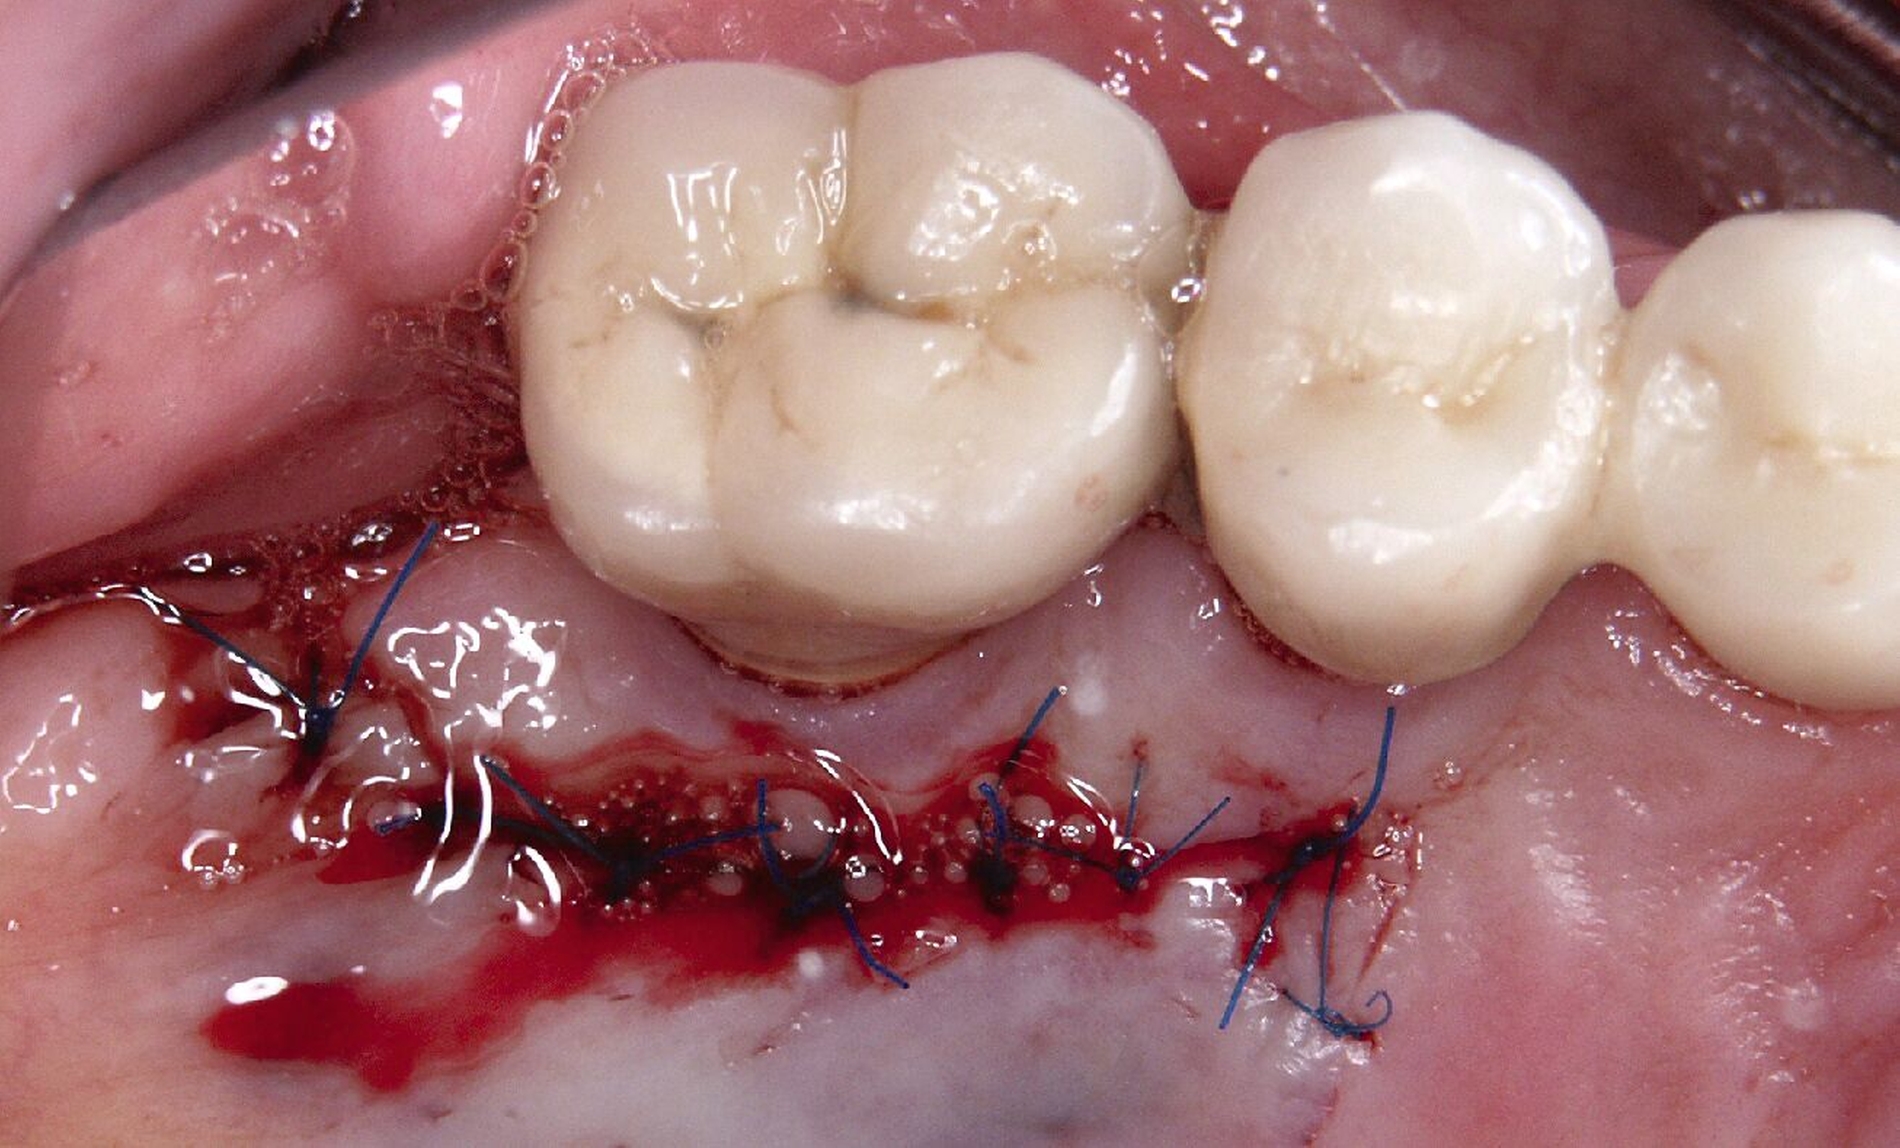

Ursprünglich waren bei dieser Patientin nach einem Frontzahntrauma vier Implantat-gestützte Kronen geplant. Nach dem frühen Verlust des Implantats in regio 21 während der Einheilzeit wurde dann eine auf drei Implantaten abgestützte Brücke eingegliedert. Das bestehende vertikale und horizontale Weichgewebsdefizit wurde bei der verschraubten Implantatbrücke durch aufgebrannte rosafarbene Keramik kaschiert (Abb. 3a). Funktionell war die Brückenversorgung über viele Jahre erfolgreich und zeigte keinerlei Lockerungsgrad. Trotz guter Mundhygiene war in Kontrollsitzungen ein kontinuierlicher Knochenabbau an allen Implantaten festzustellen (Abb. 3b). Zur Vermeidung eines weiteren Knochenverlusts fiel circa 15 Jahre nach der Erstversorgung die Entscheidung zur Explantation. Zu diesem Zeitpunkt war die Patientin 55 Jahre alt.

Nach dem Abschrauben der Suprastruktur (Abb. 3c und 3d) wurden alle Implantate unter Lokalanästhesie mit einem passenden Trepanbohrer umbohrt und ohne Lappenbildung entfernt. Die temporäre Lückenversorgung erfolgte mit einer herausnehmbaren Prothese, die über Gussklammern am Restgebiss abgestützt war.

Da sechs Monate nach der Explantation keine nennenswerte knöcherne Regeneration festzustellen war, wurde eine zweizeitige Implantation nach Knochenaugmentation mithilfe dünner Knochenscheiben aus dem Kieferwinkel geplant. Die Entnahme erfolgte mit oszillierenden Instrumenten (Piezosurgery). Der Knochenblock wurde in dünne Scheiben geschnitten und mit Osteosyntheseschrauben am Alveolarfortsatz fixiert (Abb. 3e). Darüber wurden die Weichgewebe dicht vernäht. Weitere fünf Monate später erfolgte die Schraubenentfernung und die Implantation von zwei Bone-Level-Implantaten in regio 12 und 22 mit geschlossener Einheilung (Abb. 3f und 3g). Bei der Implantatfreilegung weitere sechs Monate später wurden die Weichgewebsdefizite im Brückengliedbereich durch ein kombiniertes Bindegewebs-/Schleimhauttransplantat aufgefüllt und gleichzeitig die keratinisierte periimplantäre Gingiva und Alveloarmukosa verbreitert (Abb. 3h und 3i). Die prothetische Versorgung erfolgte erst weitere drei Monate später, nach dem Konsolidieren der Weichgewebe. Die umfangreichen Augmentationsmaßnahmen konnten das transversale Weichgewebsdefizit vollständig kompensieren, während das verbleibende vertikale Defizit zu zervikal etwas längeren Kronen und Brückengliedern führte. Aufgrund der guten Abdeckung durch die Oberlippe kann das ästhetische Ergebnis als zufriedenstellend bewertet werden (Abb. 3j bis 3l).